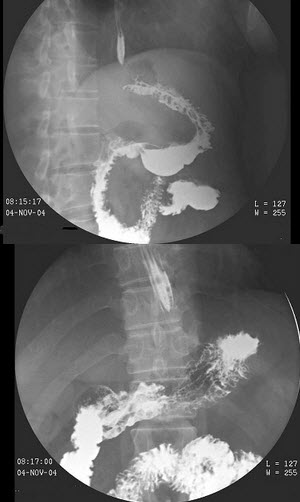

8、多项选择题 胰头癌低张十二指肠造影的X线征象为()

A.十二指肠曲扩大

B.十二指肠曲缩小

C.十二指肠内缘呈反“3”字征

D.十二指肠内缘双边征

E.十二指肠内侧呈锯齿状